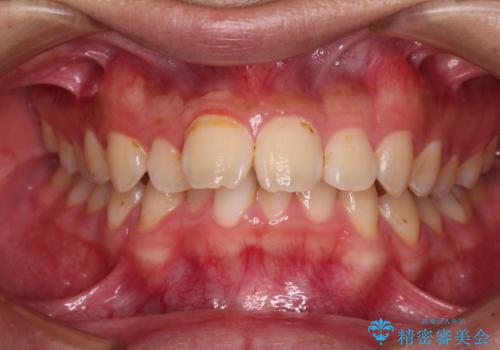

- 深く咬みこんだ前歯と、それに伴い前方に突出した上顎前歯を気にして来院された患者様です。

下顎の歯列は、奥歯が前方に傾斜し、前歯が上顎の歯の付け根に食い込むように内側に傾斜していました。

また、左右の犬歯の位置関係は上顎歯列が前方に位置する咬み合わせとなっており、インビザライン単体で治療するよりは、ワイヤー装置や補助装置を併用した方がより良い仕上がりになることが期待されました。